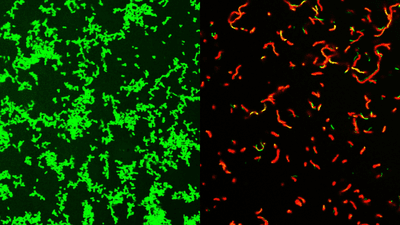

The compounds are called GmPcides (for gram-positive-icide) and had already proven their efficacy on bacteria in a Petri dish. The mouse model revealed that the compound was once again effective, both in reducing the virulence of the bacteria and even speeding up post-infection healing.

It’s not entirely clear how it’s able to do this just yet, but it’s thought that the GmPcide may affect the bacteria’s cell membranes.

“One of the jobs of a membrane is to exclude material from the outside,” said study co-author and professor of molecular microbiology Dr Michael Caparon in a statement. “We know that within five to ten minutes of treatment with GmPcide, the membranes start to become permeable and allow things that normally should be excluded to enter into the bacteria, which suggests that those membranes have been damaged.”

As well as letting in things the bacteria would sooner keep out, permeating the cell membrane can make it less able to harm the host, and less resistant to the human body’s immune response. And in case that’s not quite enough good news for you, it also proved to be effective across a range of bacteria.